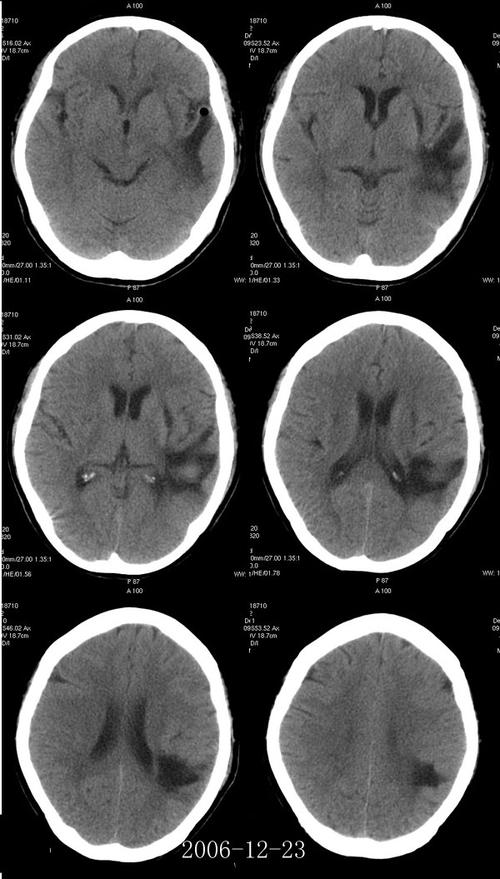

“腔隙性脑梗塞”(Lacunar Infarction)是一种特殊的、比较轻微的脑梗塞。

- 梗塞部位:它不是发生在大的脑动脉里,而是发生在大脑深部的一些非常小的穿通动脉,这些动脉的直径只有0.2-1毫米,就像一根根细小的“毛细血管”。

- “腔隙”的由来:坏死的小块脑组织被清除后,会留下一个像“小洞穴”或“小缝隙”一样的空腔,因此得名“腔隙性”。

- 病灶小:梗塞灶的直径通常在1.5-2厘米以下。